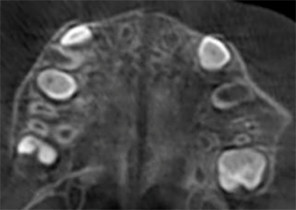

Pre Invisalign Palatal Expander Expansion

Post Invisalign Palatal Expander Expansion

After Invisalign First treatment

Pre Invisalign Palatal Expander Expansion

Post Invisalign Palatal Expander Expansion

After Invisalign First treatment

Case Report 2

7 years 11 months old, 24 stages of Invisalign® Palatal Expanders

Courtesy of Dr. David R. Boschken

Pre Invisalign Palatal Expander Expansion

Post Invisalign Palatal Expander Expansion

Post Invisalign Palatal Expander Treatment

Pre Invisalign Palatal Expander Expansion

Post Invisalign Palatal Expander Expansion

Post Invisalign Palatal Expander Treatment